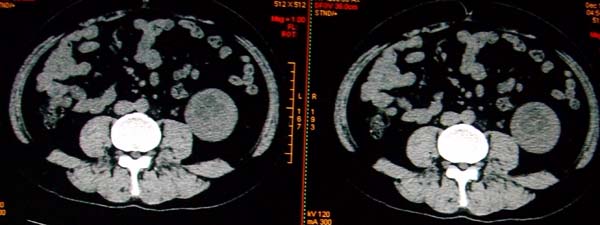

标题: CT17174:M38Y,体检超声提示右肾发育不良,病人无明显不适 [打印本页]

标题: CT17174:M38Y,体检超声提示右肾发育不良,病人无明显不适

右肾发育不良;考虑左肾下极血管平滑肌脂肪瘤可能,建议增强。

1)左肾下极占位性病变,不排除肾癌可能;建议行进一步检查。2)右肾发育不良。

左肾下极占位性病变,不排除肾癌可能;建议增强及明确内部组织ct值。右肾发育不良。

右肾发育不良。左肾代偿。左肾下极占位,性质待定,建议强化。

右肾发育不良。左肾下极囊实性占位,建议增强。